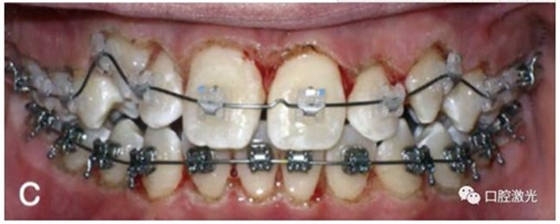

有時,會遇到一些口腔衛(wèi)生問題比較嚴重的患者,從而導(dǎo)致牙齦發(fā)炎而腫大。通過改善口腔衛(wèi)生環(huán)境,炎癥可以得到緩解,但增生的牙齦不一定都可以完全恢復(fù)。下圖的患者就存在口腔牙齦肥厚問題,同時左上部犬牙存在部分萌出的問題,右上部犬牙存在未萌出問題,這些問題都妨礙了托槽的粘接。因此,實施了全口腔的牙齦整形手術(shù)。去除了多余的牙齦組織,增加了犬牙的暴露面積,從而使托槽的粘接更為便利,同時也提升了患者保持口腔衛(wèi)生的狀況。

激光牙齦整形后即刻

激光治療當(dāng)天粘接托槽